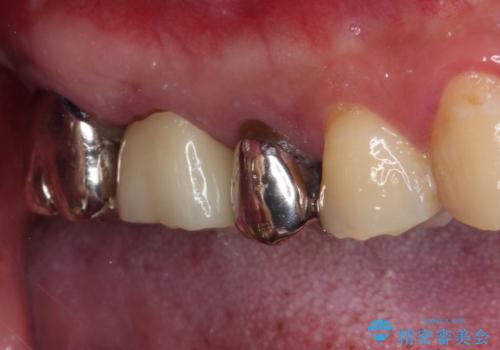

- ものが挟まるとのことで来院された患者様です。

一度は治療せずに放置していましたが、1年後のメインテナンスの際に悪化していることが分かったことから、補綴治療を行うこととしました。

神経を抜いてある歯はむし歯が進行しても痛みを感じることがないため、気がついたときには著しくむし歯が進行している可能性があります。

早めの対応とすることで、抜歯を回避できることはもちろん、外科処置などの本来必要のない処置を行わずに対処することができました。